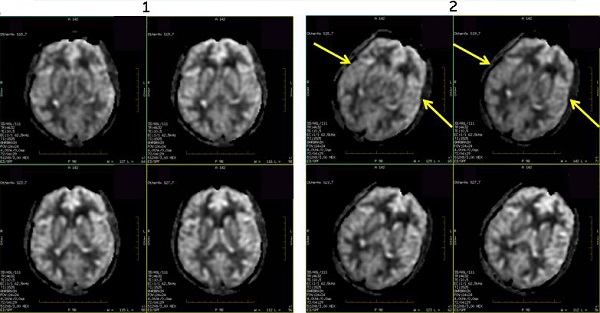

Figure 1. 3DASL images with head straight and head tilted

Table 1. Image legend

NumberDescription

1Head is positioned straight, nose up. Note the even contrast between right and left hemispheres.

2Head is tilted towards the left. Note the uneven contrast between the right and left hemispheres.